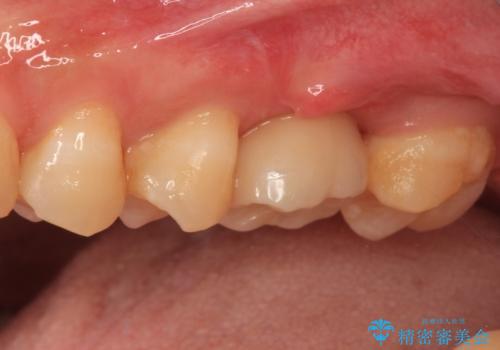

詰められた材料や壊死した組織を除去したところ、鮮明な破折線が認められたため、速やかに抜歯し、傷や骨の治癒を待って、サイナスリフトにより骨高さの低い部分にインプラント埋入を行いました。